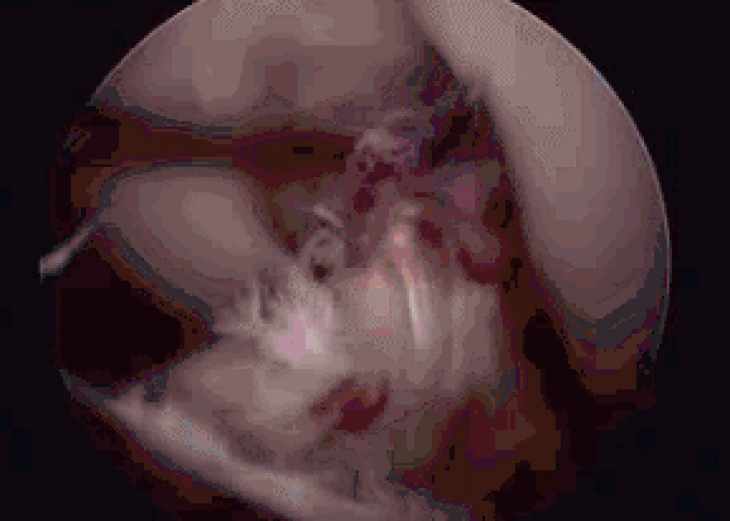

前交叉韧带(ACL)损伤的MRI诊断作者:广西中医药大学第一附属医院米琨引言前交叉韧带(ACL)损伤是青壮年膝关节最常见的运动损伤,损伤后膝关节肿胀、疼痛,活动受限。虽然肿胀消退后绝大...